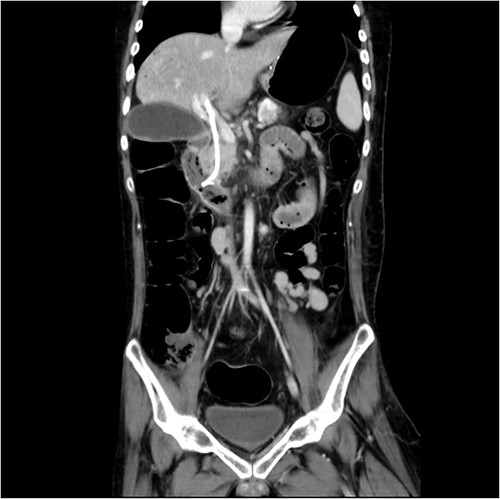

Just after ERCP, the abdominal CT showed retained contrast medium in bile duct.

Malposition of the CBD internal stent with upper portion in main portal vein.